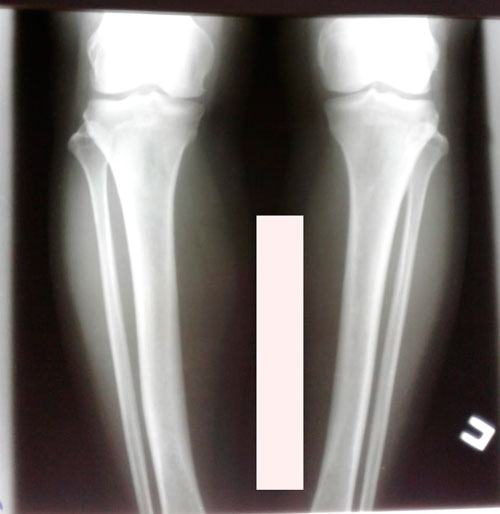

Исходник - 50 лет. Актобе

Дата операции - 09.11.2018г.

в процессе исправления деформации ног.

Дата снятия аппаратов - 12.03.2019г.

Срок сращения - 4 месяца.